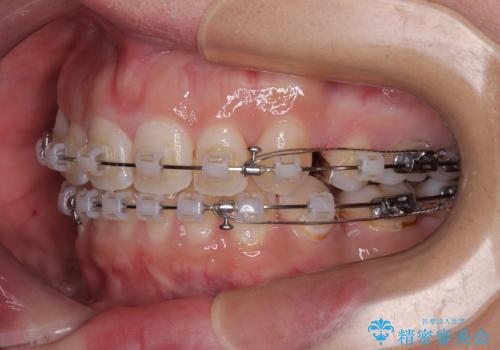

- 矯正装置

- クリアブラケット

第二小臼歯抜歯はイレギュラーな治療手段であり、治療期間が延びる傾向にありますが、予定よりも早い2年間で終えることができました。